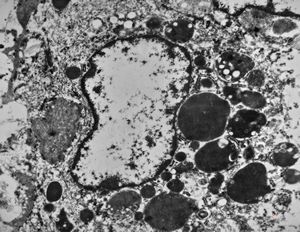

F,32y. | lymphadenopathy - clin. dysglobulinaemia